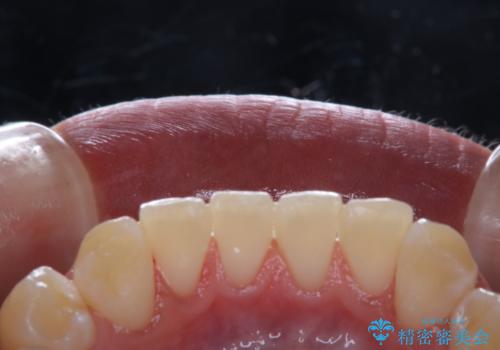

ホワイトニングせずにPMTCで明るい口元に

- ホワイトニングを考えているとのことで久しぶりに来院された方です。歯石やプラークの付着があったため、まずはPMTC60分コースを行いました。

施術後には、現状で満足とのことだったため今後は定期的なクリーニングを行っていくこととなりました。

PMTCでは、プラークや歯石、着色などを徹底的に除去します。